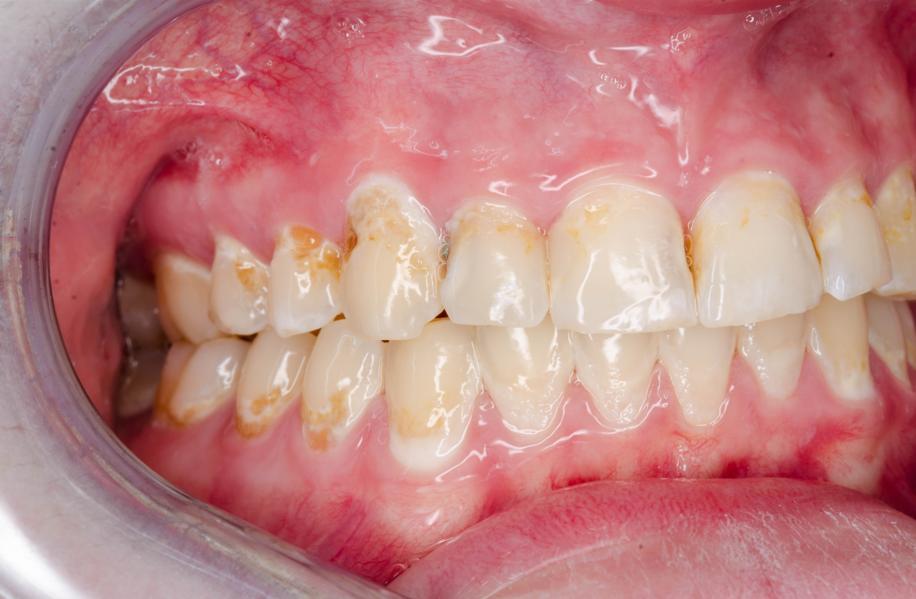

下部爲洗掉牙結石後萎縮掉的牙齦

上面爲相對健康

圖片來源:朋友友情提供